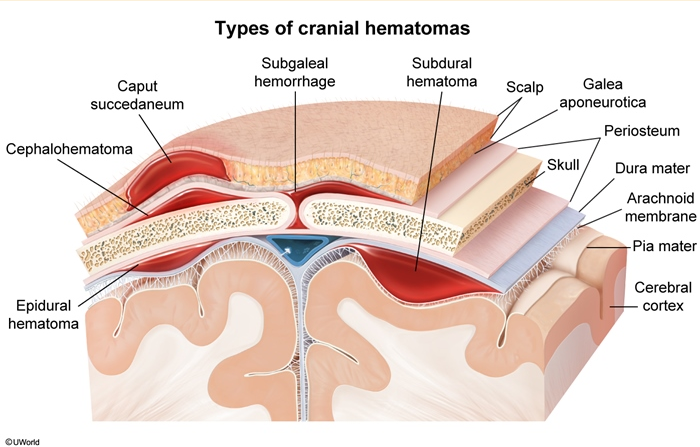

cephalohematoma is ____ bleeding

subperiosteal, does not cross suture lines - firm, nonfluctuant

subgaleal vein shearing is ___ (peds)

hemorrhage involving the dural sinuses & scalp, leading to massive blood accumulation between the periosteum and galea aponeurotica

diffuse, fluctuant scalp swelling that extends beyond suture lines and potentially to the neck; expands over 2-3 days, can lead to hypovolemic shock, DIC, and death → supportive care required